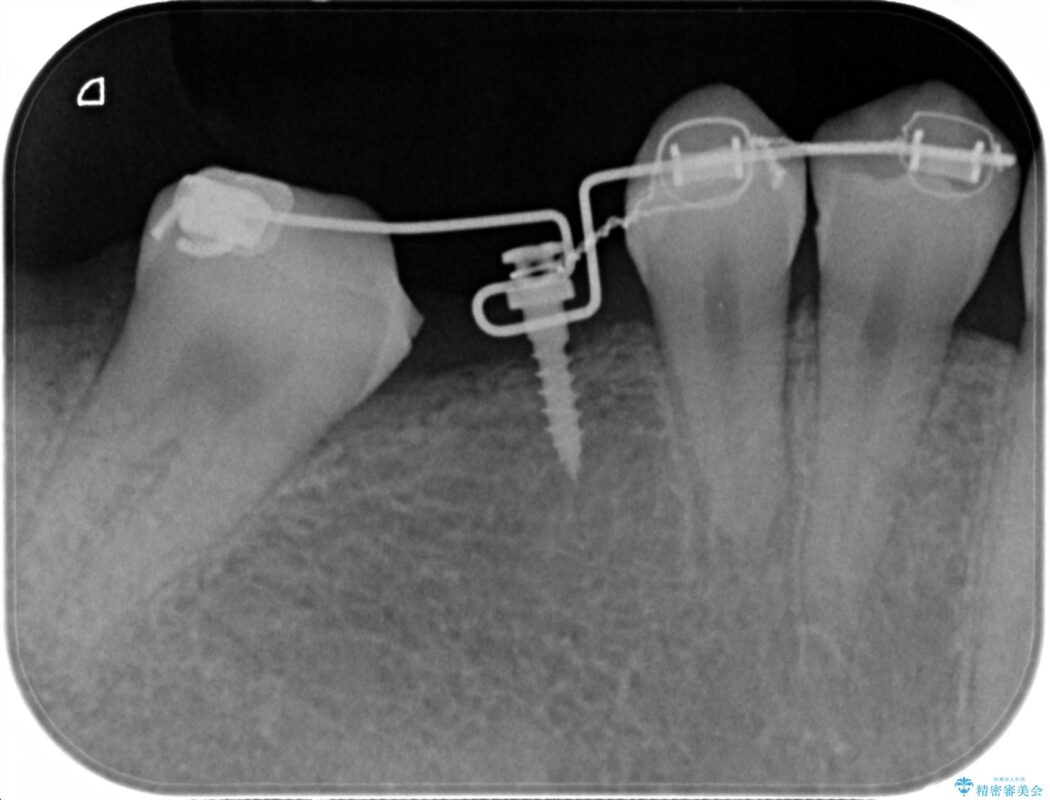

診査した結果、欠損した状態で長期間放置していたことが原因で最高峰の奥歯が欠けた部分に向かって傾斜してしまっていました。

この状態のままブリッジ治療へと進んでしまうと神経が露出する可能性が否定できないため、まずワイヤー装置による部分矯正で歯軸を通常位置へ戻してから補綴治療を行うこととしました。

本症例では、健康な歯を可及的に守るため神経の処置を避けた上で部分矯正を併用して行うことにより、安全に補綴治療(ブリッジ)ができました。